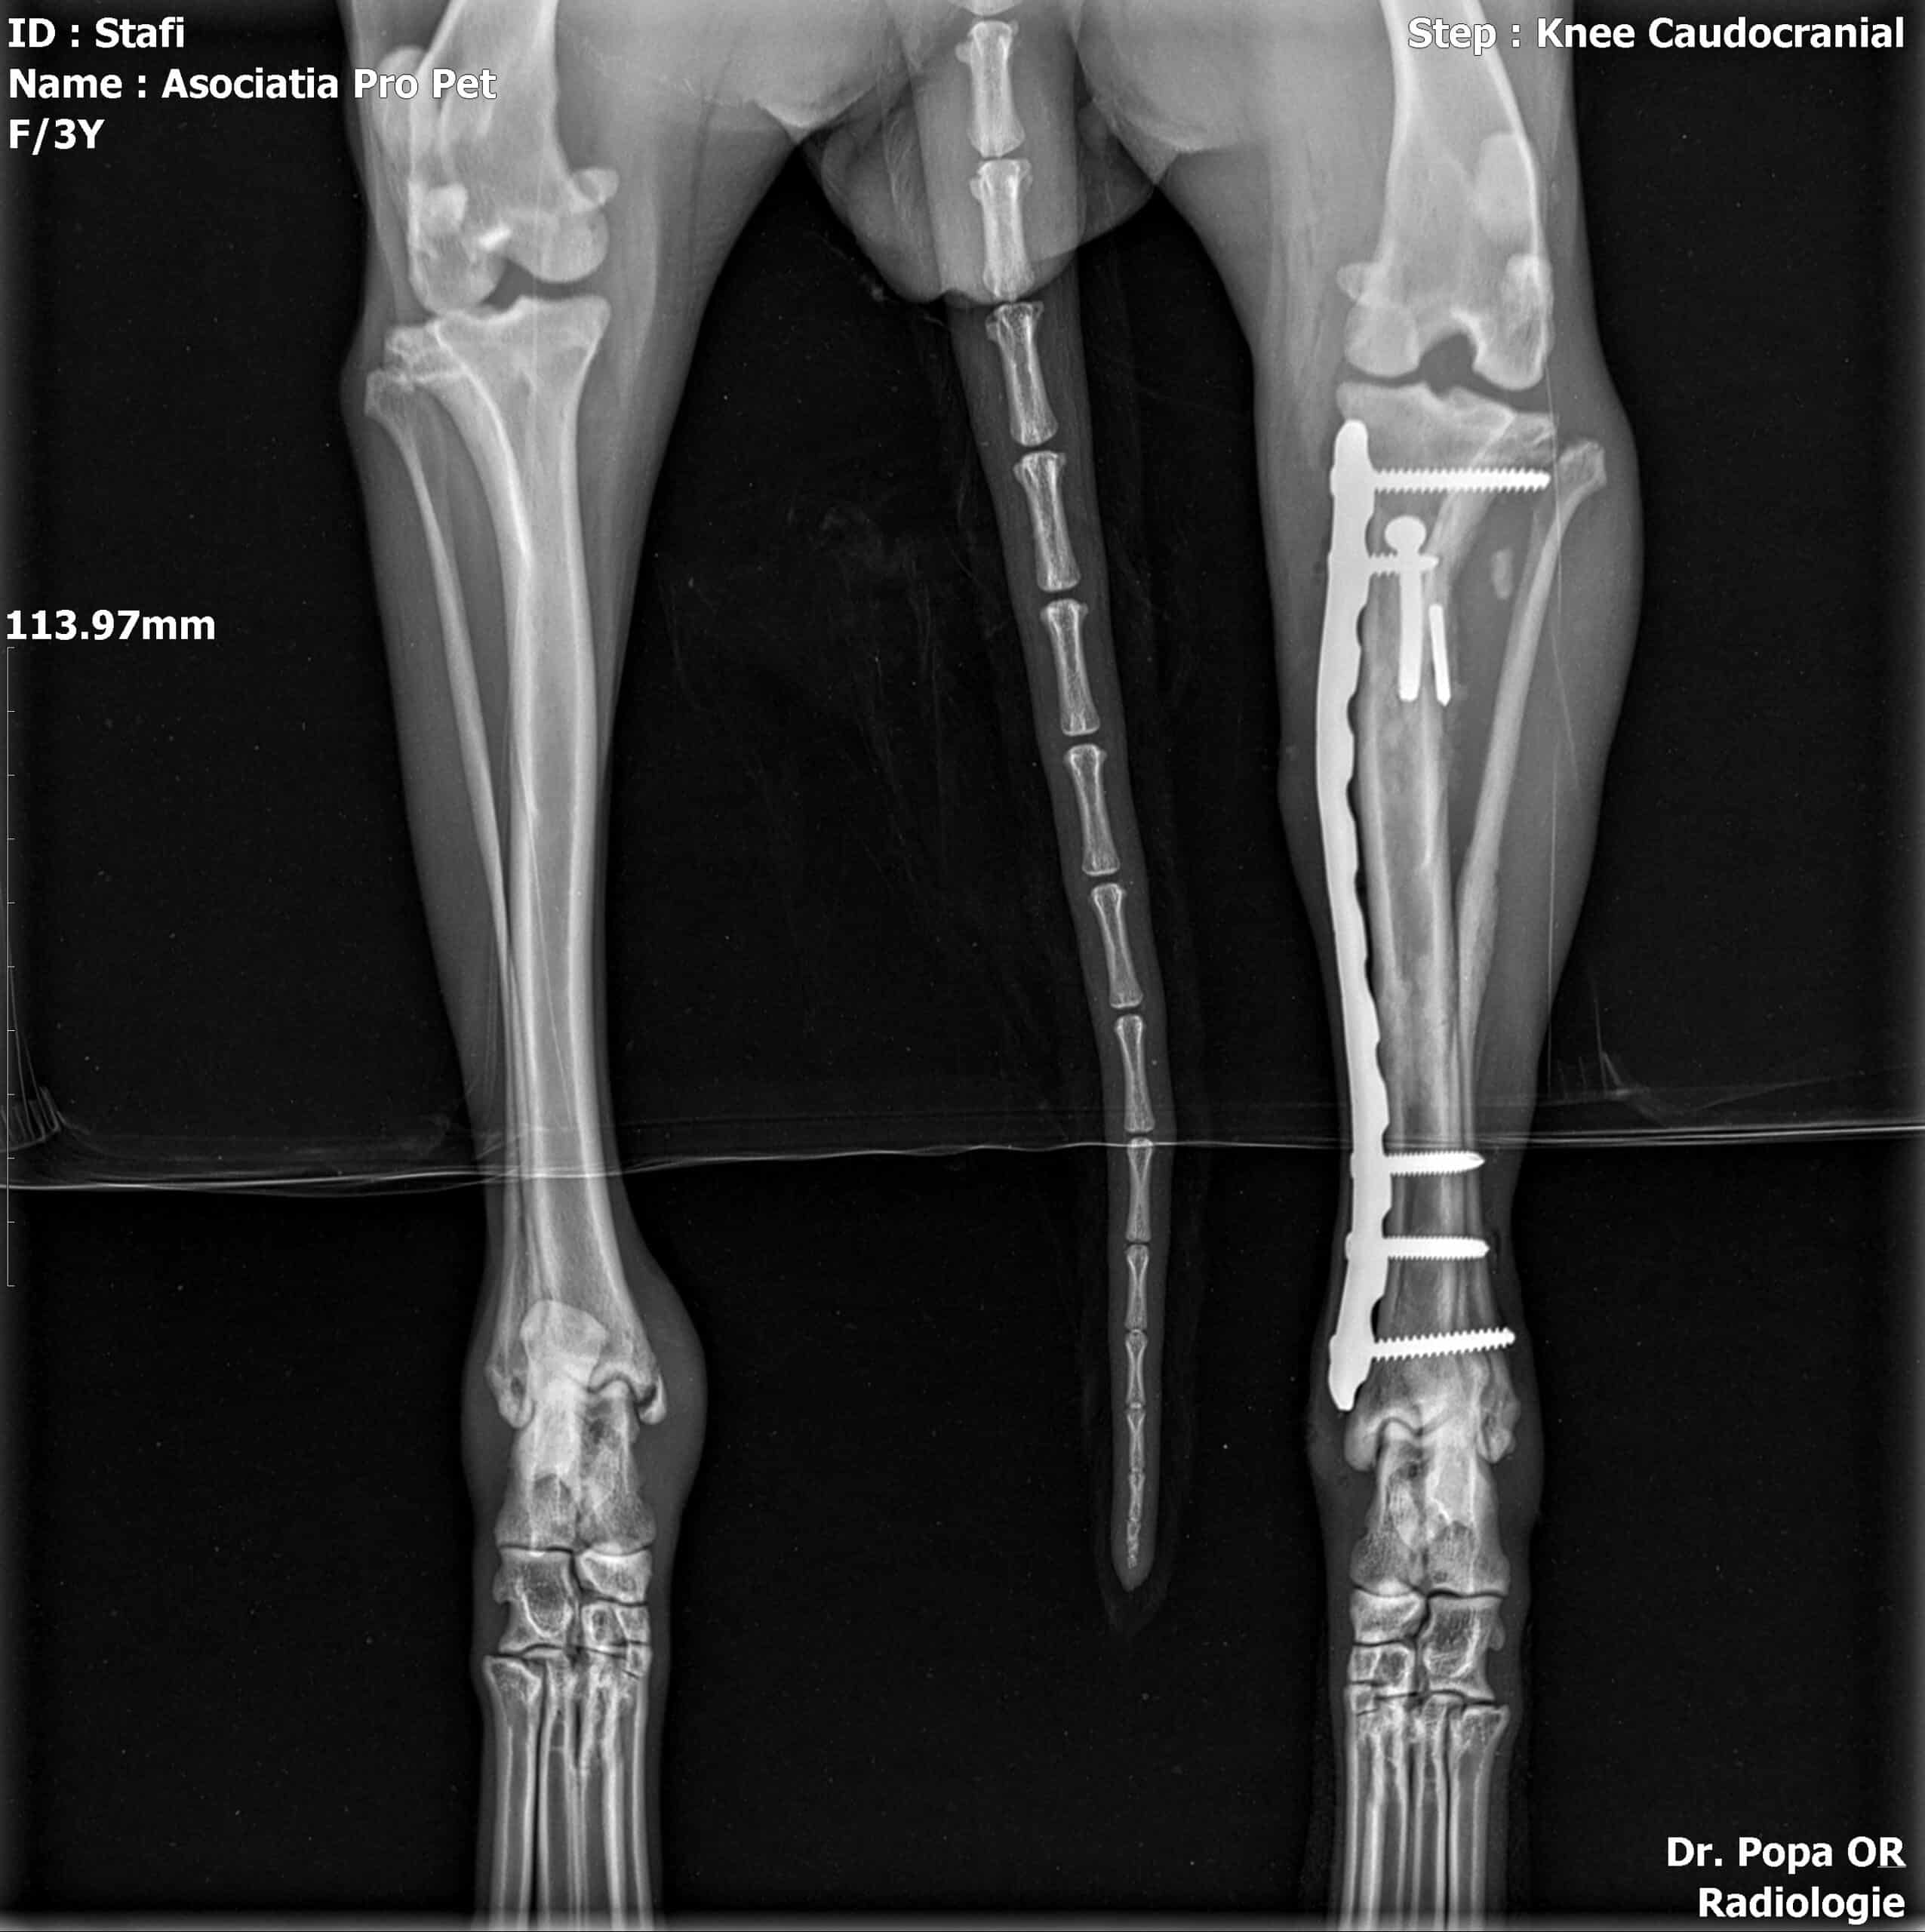

Röntgenbilder nach OP zugefügt.

JUBINA wurde angefahren und hat einen gebrochenen Hinterlauf, der zeitnah operiert wird (10/2022).

| zur Besonderheit: | Beinbruch nach Autounfall, wurde operiert, aktuell viel zu dünn (10/22) |

| zur Besonderheit: | Beinbruch nach Autounfall, wurde operiert, aktuell viel zu dünn (10/22) |